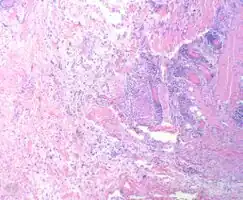

Myxofibrosarcoma-pathology

A histiocytoma is a tumour consisting of histiocytes.[1] Histiocytes are cells that are a part of the mononuclear phagocytic system, a part of the body's immune system that consists of phagocytic cells, which are responsible for engulfing solid particles by the cell membrane to form an internal phagosome by phagocytes and protists.